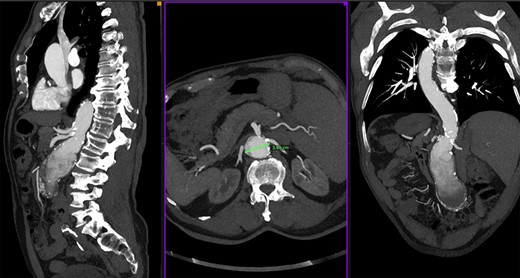

We report a case of a 73-year-old man with known SIT and past medical history of hypertension and dyslipidemia, no other comorbidities (ASA referred to our center for a specific abdominal pain); an US exam was performed, and an abdominal aortic aneurysm (AAA) was found. A followed computed tomography scan showed a 6 × 7 cm pararenal aortic aneurysm (pAAA). The pAAA was extended caudally to the aortic bifurcation with no evidence of rupture (Fig. 1). The diameter of the aorta at lower left renal artery was of 36 mm. The origins of the others visceral vessels were very close and in a short aortic segment. As we usually make for complex aortic cases, a careful multidisciplinary evaluation of comorbidities was performed. Therefore we have proposed an open repair with supraceliac clamping and visceral protection with left–left (anatomically right) heart bypass (LHB). Operation room setup, patient–surgeon position and pump placement were mirrored as compared to routine thoraco–phreno–laparotomy access (Fig. 2). Under general anesthesia, both surgical right axillar and femoral arteries were prepared. We used the axillar artery for the LHB in-line. The femoral artery was prepared for the line-out of the shunt in eventual need of total thoracoabdominal replacement with a long-time perfusion. By a right retroperitoneal approach, we prepared the aorta up to below the diaphragm. Pillars of the diaphragm were sectioned to prepare the better site to clamp the aorta. After systemic heparinization, the aorta was clamped above the celiac trunk. The aorta was opened; both renal arteries, superior mesenteric artery and celiac trunk were cannulated with 9-Fr Pruitt catheters connected to the pump. Therefore, the visceral vessels and the renal arteries were perfused with isothermic blood from the LHB circuit (Medtronic Biomedicus 560 centrifugal pump). Both common iliac arteries were endo-clamped with Fogarty catheters. The left renal artery was disconnected, and an oblique end-to-end anastomosis between the proximal aorta (including the visceral vessels and the right renal artery takeoffs) and a straight 18-mm Dacron graft was performed. The distal anastomosis was constructed at the level of the aortic bifurcation, and subsequently the left renal artery was replaced on the tube graft with T-L anastomosis (Fig 3). Postoperative course was uneventful, and the patient was discharged on 6th postoperative day. Follow-up CT scan 6 months after the intervention showed a good treatment of the aneurysm with a patency of all visceral vessels (Fig. 4).